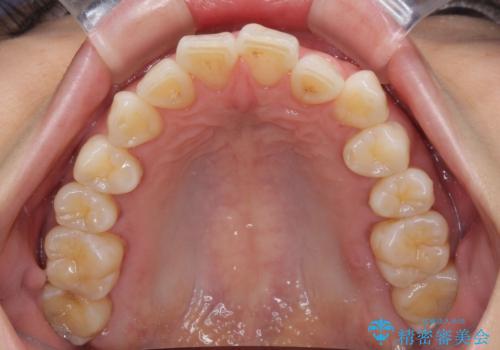

- 奥歯の咬み合わせと、上下前歯の隙間を気にして来院された患者様です。

上顎の歯列全体が、下顎歯列に対して前方に位置しており、その影響で上顎前歯がやや前方に突出している状態でした。

横顔の印象から、抜歯をして積極的に口元を引っ込める必要はなかったため、アンカースクリューを用いて上顎歯列全体を後方に移動させることとしました。

奥歯の咬み合わせは理想的な状態に改善され、その結果として上下歯列もバランスの良い位置に収めることができました。

若干ではあるものの上顎前歯を内側に移動させることができ、以前よりも口が閉じやすいと感じるようになりました。